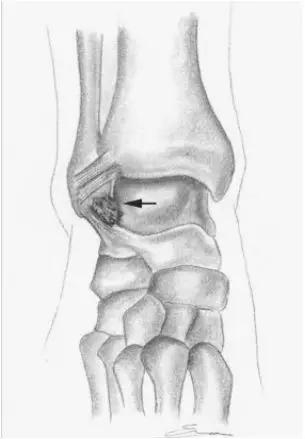

- 又称足球踝,通常为骨性撞击,由于经常性背屈导致胫骨远端关节面前缘与距骨颈部上缘骨赘反复撞击,有时滑膜软骨瘤病的游离体聚积在关节囊前部也会导致前撞击综合症。

- 放射学表现主要为胫骨前下缘与距骨颈部前上缘鸟嘴样骨刺形成。

放射学表现主要为胫骨前下缘与距骨颈部前上缘鸟嘴样骨刺形成